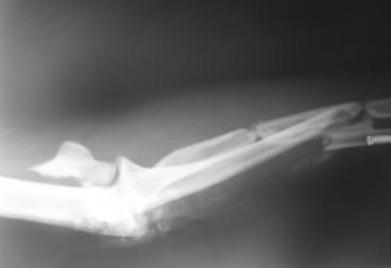

Больной Б. 43 лет, находится в клинике с диагнозом: Автотравма от 17.12.08 г. Открытый (3а) оскольчатый чрезмыщелковый перелом левой плечевой кости, закрытые оскольчатые переломы диафизов костей левого предплечья. Травму получил в Ленинградской области, доставлен в одну из районных больниц, где выполнена ПХО раны, начата АБ-терапия. Переведен к нам в клинику через сутки после травмы для оперативного лечения. Рана длинной около 8-10 см по задне-наружной поверхности плеча, без признаков воспаления. Планируется сначала выполнить остеосинтез локтевой кости пластиной DCP, затем остеосинтез плечевой кости по внутренней поверхности пластиной, по наружной - винтами, после остеосинтез лучевой кости LCP пластиной. Какие альтернативные методы лечения возможны в данной ситуации?